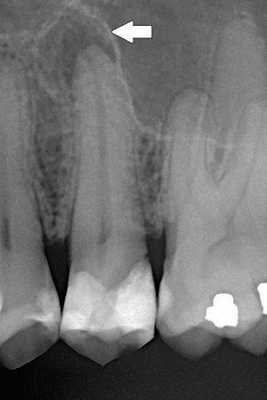

При перкуссии 2.6 зуба отмечается боль. Симптом нажатия положительный, что является одним из признаков отличия ложно-положительной перкуссии при симптоматическом пульпите. Самое интересное — фриз тест (реакция на холод): результат резко положительный, длительно сохраняющийся. При удалённом нерве такой реакции быть не должно, поэтому все ещё скептически отношусь к этому зубу, подозреваю скрытую кариозную полость на соседних зубах. Их электроодонтодиагностика в пределах нормы, а 2.6 реагирует на пульпитные значения. Решено провести рентген, в итоге обнаружена пломба, какая-то еле заметная тень в каналах на 1/2 длины и очаги деструкции на верхушках корней. Соседние зубы интактны. Это подтверждает предположение о "Red russian cement". Но причем тут боли от температурных раздражителей?

- Дентальная рентгенография. Нередко радикулярная киста выявляется случайно в процессе лечения других зубов. Данное образование на рентгенограмме представляет собой круглую или овальную тень с четкими границами, расположенную у верхушки корня зуба или прилежащую к боковой стенке корня. Костная структура периодонтальной щели разрушена и на снимке не визуализируется. Корни соседних зубов смещены. В ряде случаев идентифицировать кисту не удается даже на рентгеновском снимке, из-за того что корень причинного зуба попадает в зону видимости недостаточно полно.

КТ челюстно-лицевой области. Радикулярная киста (красная стрелка) вблизи корня левого клыка верхней челюсти, состояние после эндодонтического лечения (синяя стрелка - филлер в корневом канале), избыток филлера за пределами верхушки зуба (зеленая стрелка).